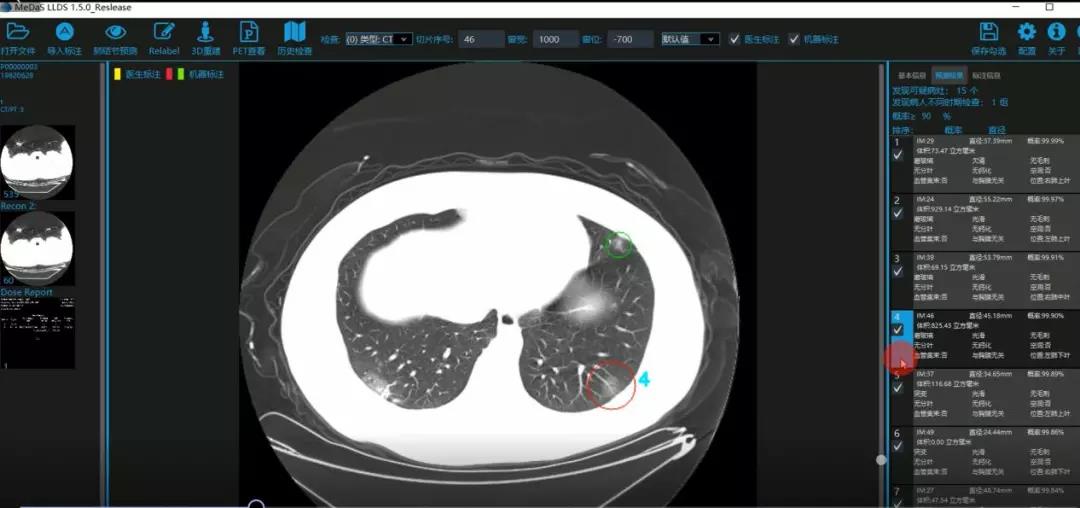

医护人员的好帮手:基于深度学习的新冠肺炎早期检测筛查系统

西电今年会官方网站智能软件与系统新技术研究所副教授张亮的爱人是西安交通大学第二附属医院抗疫一线的影像科医生,疫情发生以来,他们讨论最多的就是新型冠状病毒感染者的早期诊断问题。作为一名医护家属,身为高校科研工作者,张亮深知快速准确地诊断新冠肺炎早期患者对控制和防治疫情的重要性和挑战性。他与团队成员主动出击,通过远程网络会议,在前期医学影像处理的研究基础上加速科研攻关,反复讨论方案,屡次设计模型,与上海宽带技术及应用工程研究中心、上海交通大学医学院附属瑞金医院等合作单位的人员多次标注整理患者肺部CT影像数据到深夜。与此同时,他们依托上海瑞金医院、西安交通大学第二附属医院等的新冠肺炎疑似、确诊患者肺部CT影像,通过综合分析新冠肺炎患者的肺部CT影像特点(磨玻璃、体积大小、位置等特征),张亮团队加快技术攻关,设计开发了基于深度学习的新型冠状病毒的早期检测筛查模型系统。

对应新冠肺炎CT病灶检测效果

令人欣喜的是,通过对实际门诊数据排查测试,该模型可以减轻医护人员近80%的工作量,新冠肺炎患者的检测召回率超过95%。目前,模型系统正在进行最后的调试工作,很快投入到“战疫”一线,缓解医护人员紧缺、确诊检测工作耗时较长等问题,减少医护人员的工作时间和劳动强度,提高工作效率。